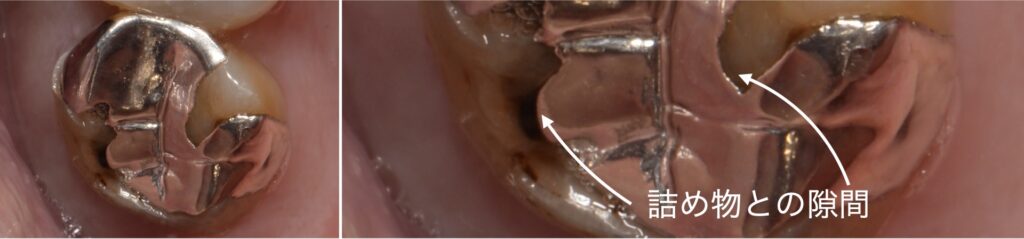

上記左側の写真のように、一見封鎖性のよい詰め物に見えたとしても、右側写真のように歯科用顕微鏡(マイクロスコープ)を用いた拡大写真を見ると、隙間にプラークが入り込んでいることがわかるかと思います。

細菌の大きさは約1ミクロンから3ミクロンと言われており、これは1000分の1ミリから1000分の3ミリです。

細菌が侵入できないような精度の高い詰め物を作製することは並大抵なことではないとわかると思います。